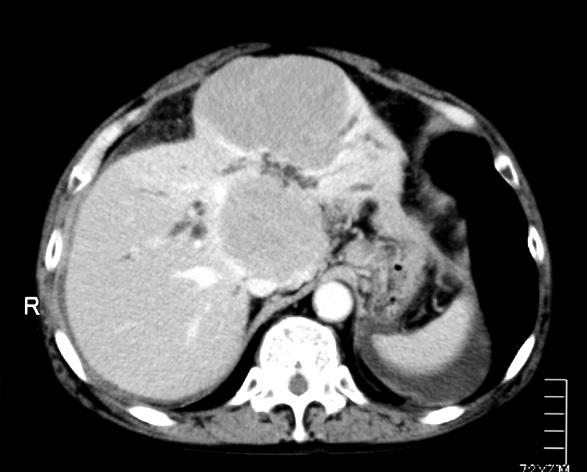

livertumor.jpg

72歳 男性

腹部膨満感で他院を受診. 黄疸と心窩部腫瘤を触れCTでは管内胆管の拡張と左葉の腫瘤を認めた。精査治療のため当院消化器内科を紹介される。 ENBD留置などの処置で減黄を行う。ERCPによる胆汁細胞診では少数のatypical lymphcytesを認めるが確診できず。肝生検をおこなった。

既往歴:1年前肝右葉の肝膿瘍。ドレナージで治癒。組織の採取は行っていない。